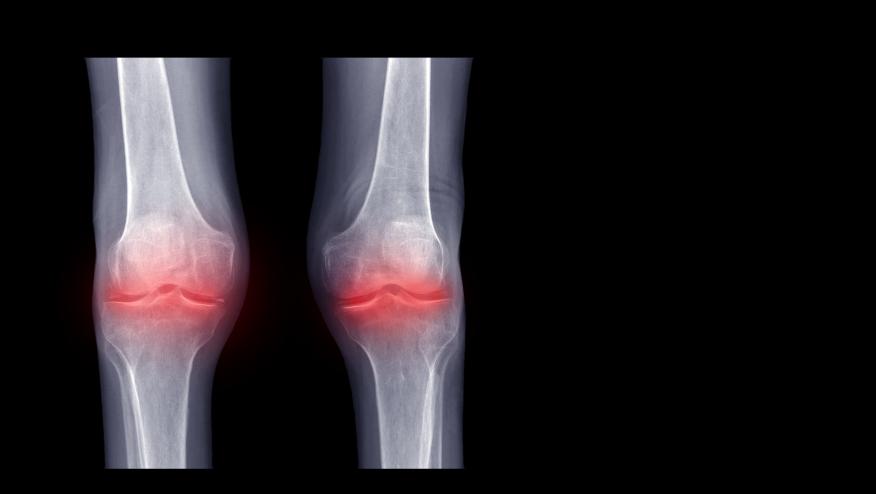

The COLCHICORT trial in acute calcium pyrophosphate (CPP) crystal arthritis patients showed that colchicine was inferior to prednisone treatment and that responses were also influenced by other factors.

A post hoc analysis of the COLCHICORT trial, which compared colchicine and prednisone for the treatment of acute CPP arthritis, also examined associations with sustained arthritis resolution on day 3.